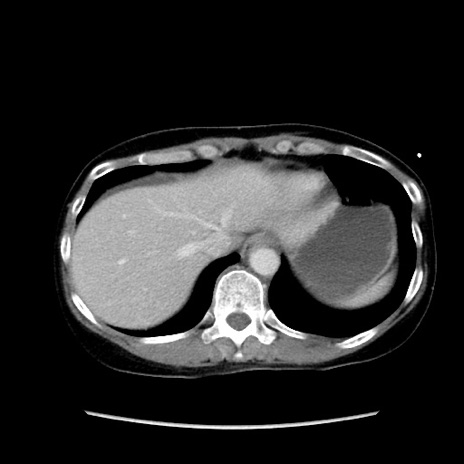

症例32(横断像)

【症例】40歳代 女性

【主訴】上腹部痛、嘔気・嘔吐

【現病歴】約9時間前頃から急に上腹部痛、嘔気、嘔吐が出現。改善しないため救急要請。

【既往歴】子宮頚癌(広汎子宮全摘術、放射線療法)、腸閉塞

【身体所見】腹部:平坦、軟、腸雑音亢進、上腹部を中心に腹部全体に圧痛あり。

【データ】WBC 8400、CRP 0.03